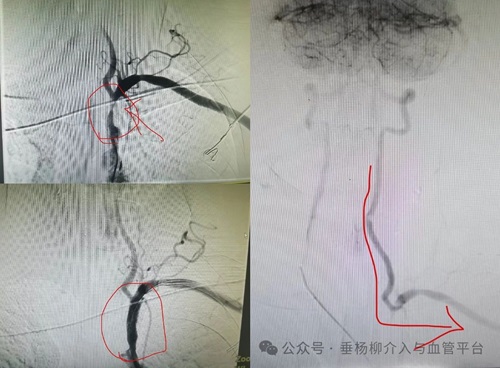

如果突然感到腿部冰凉、麻木、疼痛,特别是持续性疼痛,腿部皮肤变苍白或青紫,感觉像是血液流通被阻断。这可能是动脉栓塞的警报。动脉栓塞是一种急症,若出现上述症状,应立即就医,防止组织坏死和严重并发症。

9. 腹部搏动性包块:可能是腹主动脉瘤